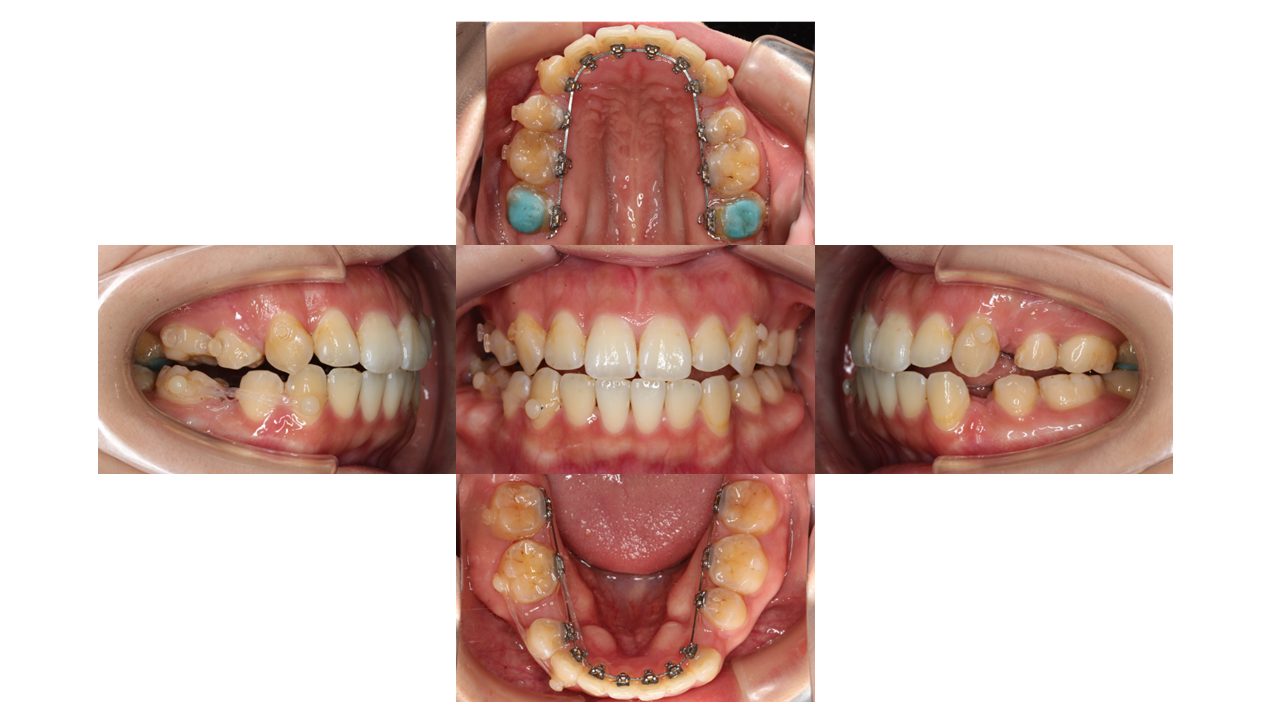

9か月経過の口腔内の状態です。

全体の凸凹が改善されました。

ゴムの力を使って、抜歯したスペースを閉じていきます。